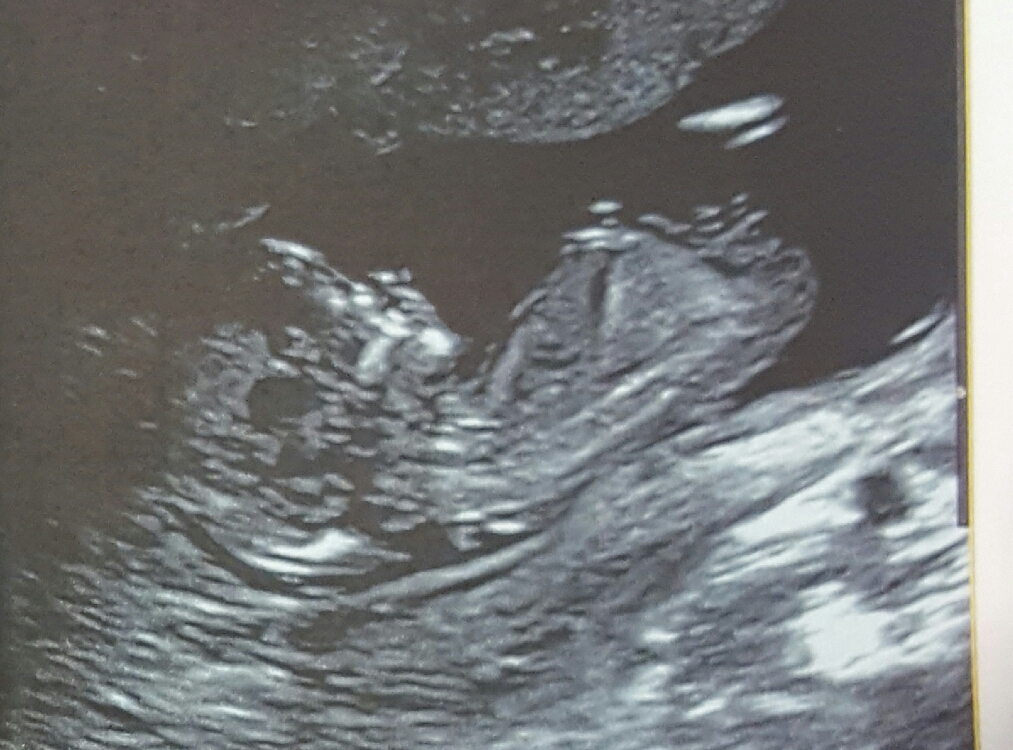

I am currently 13 weeks pregnant, well just over that and have had two scans in last three days due to baby playing up at scans. Wondering if anyone might be able to guess what gender baby is from these pictures as scan lady wouldn't check properly.

Attachment 33294Attachment 33295Attachment 33294Attachment 33295